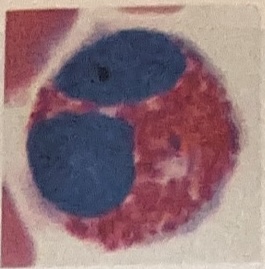

Monocytes

Largest WBC; 2-3X larger than RBCs

Cytoplasm nearly clear

Nucleus round, kidney-shaped, oval, or lobed